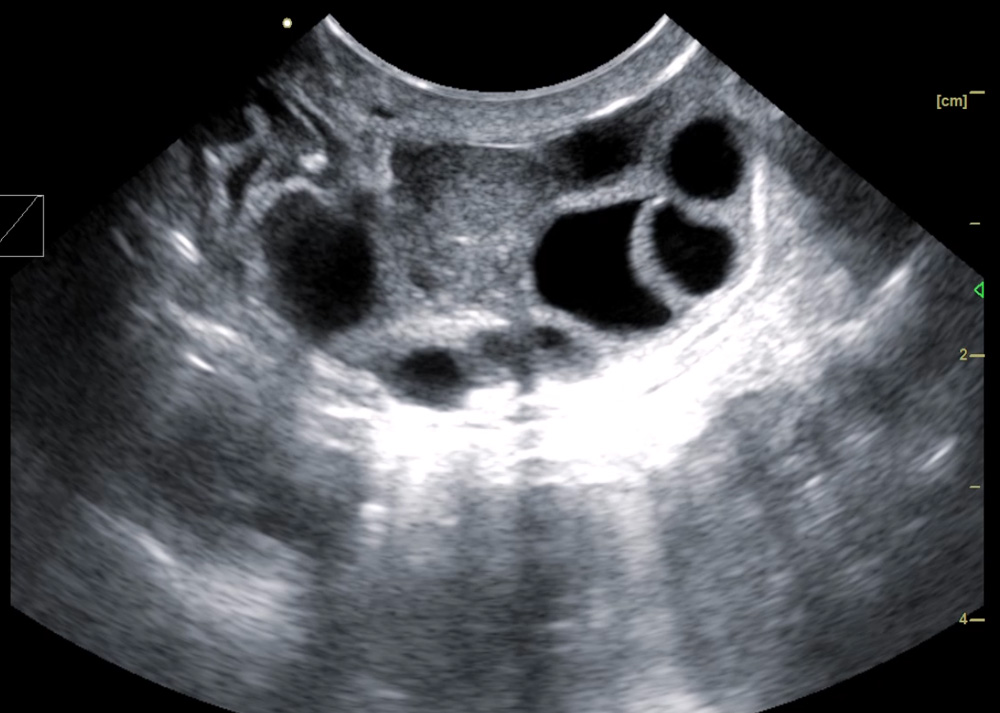

1. Animal OPU live egg collection probe:

1.1. Frequency 5.0-9.0MHz, non-porous, smooth surface, eagle-beak-shaped integrated micro-convex probe

1.9. There is an egg collection needle guide line when collecting eggs, there is a scale ruler on the egg collection needle guide line, there is a center line on the egg collection needle guide line, and the image is enhanced when the egg collection needle is punctured

1. The eagle-beak-shaped integrated micro-convex live egg collection probe is a product carefully designed according to the clinical practice of the ranch. It has passed the clinical tests of technical experts in the field of animal reproduction for multiple OPU embryo transplantation. It is convenient for clinical operation and has a high egg collection efficiency.

4. There is an egg collection needle guide line when collecting eggs, a scale ruler on the egg collection needle guide line, a center line on the egg collection needle guide line, and an image enhancement design when the egg collection needle is punctured, which can greatly improve the direction sense and strength control of the needle during egg collection.

6. High-frequency probe and high-quality Doppler color ultrasound images can observe the situation of follicles below 1mm.